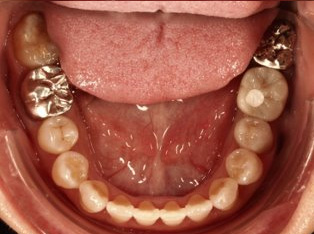

治療前

治療終了前